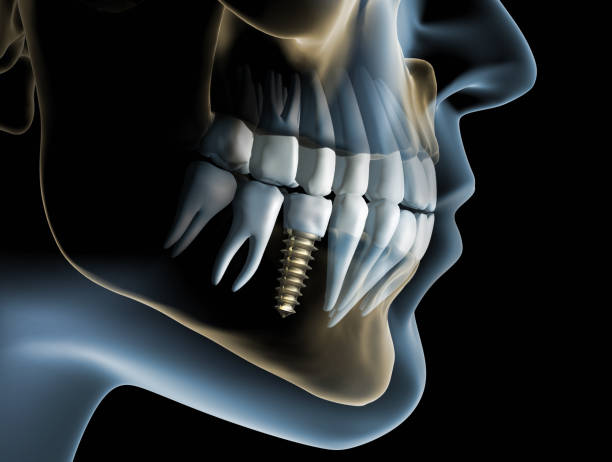

ایمپلنت یک روزه، همانطور که از نامش پیداست، روشی است که در آن کاشت ایمپلنت و نصب روکش دندان، در یک جلسه انجام میشود. در روشهای سنتی ایمپلنت، پس از کاشت ایمپلنت، باید چند ماه صبر کرد تا استخوان فک به ایمپلنت جوش بخورد (فرآیندی به نام استئواینتگریشن) و سپس روکش دندان نصب شود. اما در ایمپلنت یک روزه، این فرآیند تسریع شده و بیمار میتواند در همان روز کاشت ایمپلنت، دندان جدید خود را دریافت کند. برای درک بهتر نحوه عملکرد ایمپلنت یک روزه، مراحل زیر را در نظر بگیرید

- کاشت ایمپلنت در این مرحله، ایمپلنت (پایه تیتانیومی دندان) با استفاده از جراحی، در استخوان فک قرار داده میشود.

- نصب روکش دندان پس از کاشت ایمپلنت، روکش دندان (قسمت قابل مشاهده دندان) بر روی ایمپلنت نصب میشود. در ایمپلنت یک روزه، روکش دندان معمولاً به صورت موقت است و پس از چند ماه، با روکش دائمی جایگزین میشود.

- کاشت ایمپلنت در این مرحله، ایمپلنت با استفاده از جراحی، در استخوان فک قرار داده میشود. این عمل معمولاً تحت بیحسی موضعی انجام میشود.

- نصب روکش دندان پس از کاشت ایمپلنت، روکش دندان بر روی ایمپلنت نصب میشود. در ایمپلنت یک روزه، روکش دندان معمولاً به صورت موقت است و پس از چند ماه، با روکش دائمی جایگزین میشود.